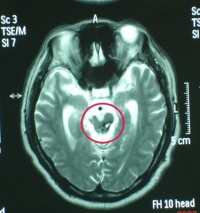

右侧颞叶脑挫裂伤

,区别只在于何者为重或何者为轻的问题。通常脑表面的挫裂伤多在暴力打击的部位和对冲的部位,尤其是后者,总是较为严重并常以额、颞前端和底部为多,这是由于脑组织在颅腔内的滑动及碰撞所引起的。脑实质内的挫裂伤,则常因脑组织的变形和剪性应力引起损伤,往往见于不同介质的结构之间,并以挫伤及点状出血为主。

MRI(磁共振成像[编辑 | 编辑源代码]

一般少用于急性颅脑损伤的诊断。MRI成像时间较长,某些金属急救设备不能进入机房,躁动病人难以合作,故多以CT为首选检查项目。但在某些特殊情况下,MRI优于CT,如对脑干、胼胝体颅神经的显示;对微小脑挫伤灶、轴索损伤及早期脑梗死的显示;以及对血肿处于CT等密度阶段的显示和鉴别诊断方面,MRI有其独具的优势,是CT所不及的。